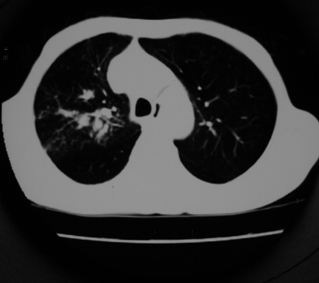

以下是引用同在2007-1-27 14:13:00的发言:[br]支持右侧中央型肺癌伴阻塞性病变.

以下是引用zjzjr在2007-1-27 16:56:00的发言:[br]支持右肺中心型肺癌伴阻塞性肺炎.